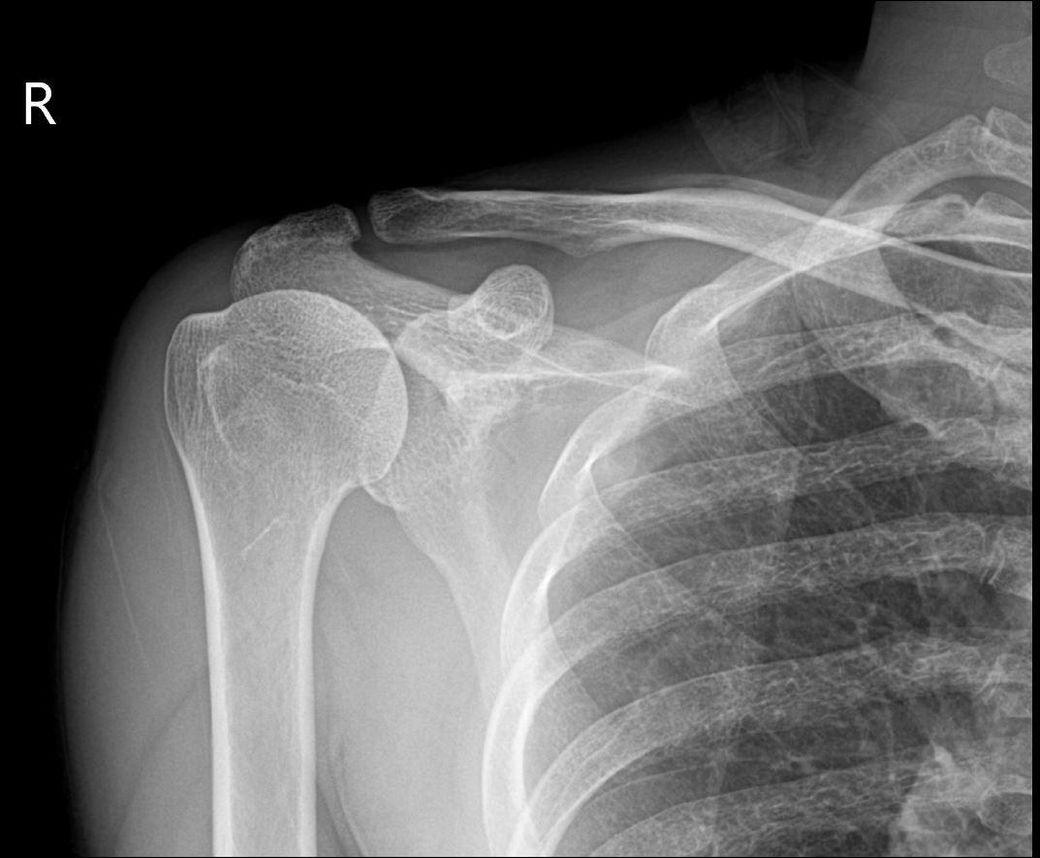

엑스레이 사진상 어깨탈구 소견이 있나요?

하기 사진은 그날 찍은 어깨 엑스레이입니다.

혹시 엑스레이상 어깨 탈골 소견이 있는지 궁금합니다.

업로드 하신 어깨 엑스레이 사진에는 딱히 보이는 이상소견이 따로 있지 않습니다. 어깨 부위 탈구 소견이 관찰되지 않으며 정상 어깨 엑스레이 사진으로 보입니다. 어깨의 탈구가 있으면 심한 통증과 함께 움직임에 제한이 생기므로 단순히 소리가 나는 소견만으로는 탈구에 대해서 크게 걱정을 할 필요는 없습니다.

우선 엑스레이 판독 결과 전문의에 소견은 탈구가 없다하셨고 사진상으론 제한이 있지만 탈구로 의심이 가진않습니다.

올려주신 어깨 엑스레이를 보면 뼈구조가 정상적으로 위치하고 있으며 명백한 탈구나 골절 소견은 보이지 않습니다. 어깨 관절은 비교적 안정적인 상태로 보입니다. 다만 어깨에서 뚝소리가 나는 것은 관절이나 힘줄, 인대가 움직이면서 나는 소리일 수 있으며 반드시 탈골을 의미하지는 않습니다! 통증이 없고 움직임도 정상적이라면 큰 문제 가능성은 낮습니다!안녕하세요. 김현태 물리치료사입니다.